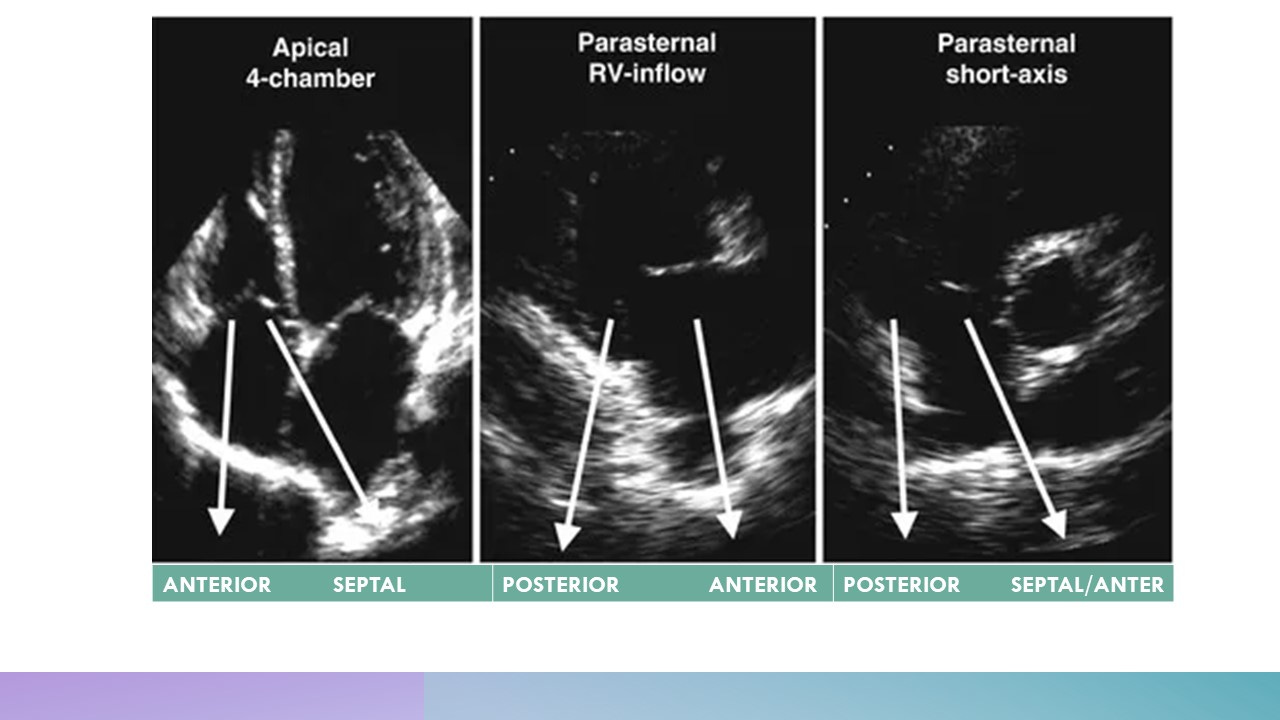

Which view shows which Leaflet of TCV:

Which view shows which leaflet of TCV